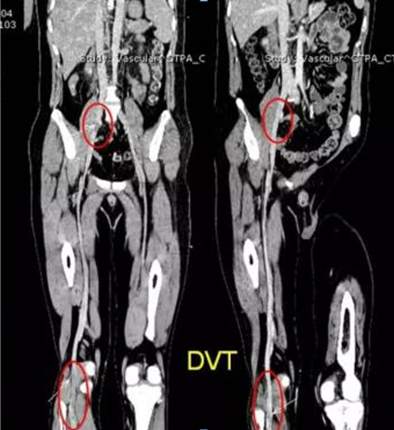

全身大血管CT血管造影检查通过注射造影剂、利用CT螺旋扫描在受检者靶血管内对比剂充盈的高风期进行连续的原始数据容积采集,然后利用计算机的后处理功能、如多方位重组(MPR)、最大密度投影(MIP)、容积再现重组(VR)、表面遮盖法重建技术(SSD)等重建靶血管,形成成像的血管影用于血管疾病的诊断,是发现动脉夹层、血管瘤/评价血管狭窄情况的神奇工具。